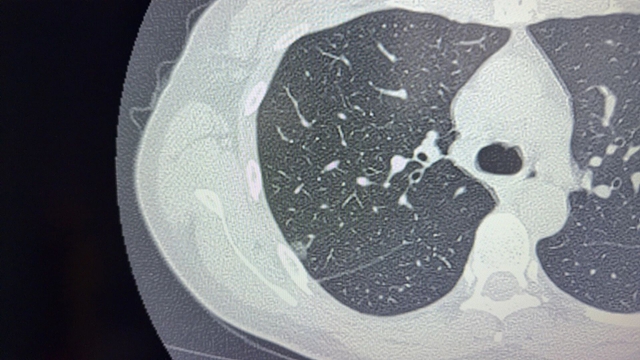

今年2月,复查胸部CT传来坏消息:原有结节不仅增大,形态还变得不规则,右肺下叶还新增了一个小结节。医生建议尽快手术,可传统开胸手术的大切口、全麻插管风险,以及漫长恢复期,让她迟迟不敢下决心,纠结了整整大半年。

单孔胸腔镜仅需在胸部打一个2-3厘米的小切口,借助高清内镜精准切除结节,创伤极小,刘浩副教授耐心地解释,让刘女士彻底放下心防。10月28日,她顺利入院,术前检查就绪后,刘浩团队制定了精准手术方案。

手术室里,胸心外科刘浩团队凭借丰富的经验和精湛技术,通过单孔胸腔镜在高清视野下精准定位双肺结节。无需考虑全麻插管对呼吸的影响,手术操作灵活高效。

10月30日早上,复查结果出炉:肺部通气正常,切口愈合良好,血常规指标全部正常,无任何并发症。病理检查显示,切除的结节为恶性肿瘤,但因发现及时、切除彻底,切缘干净,无需后续放化疗,定期复查即可。